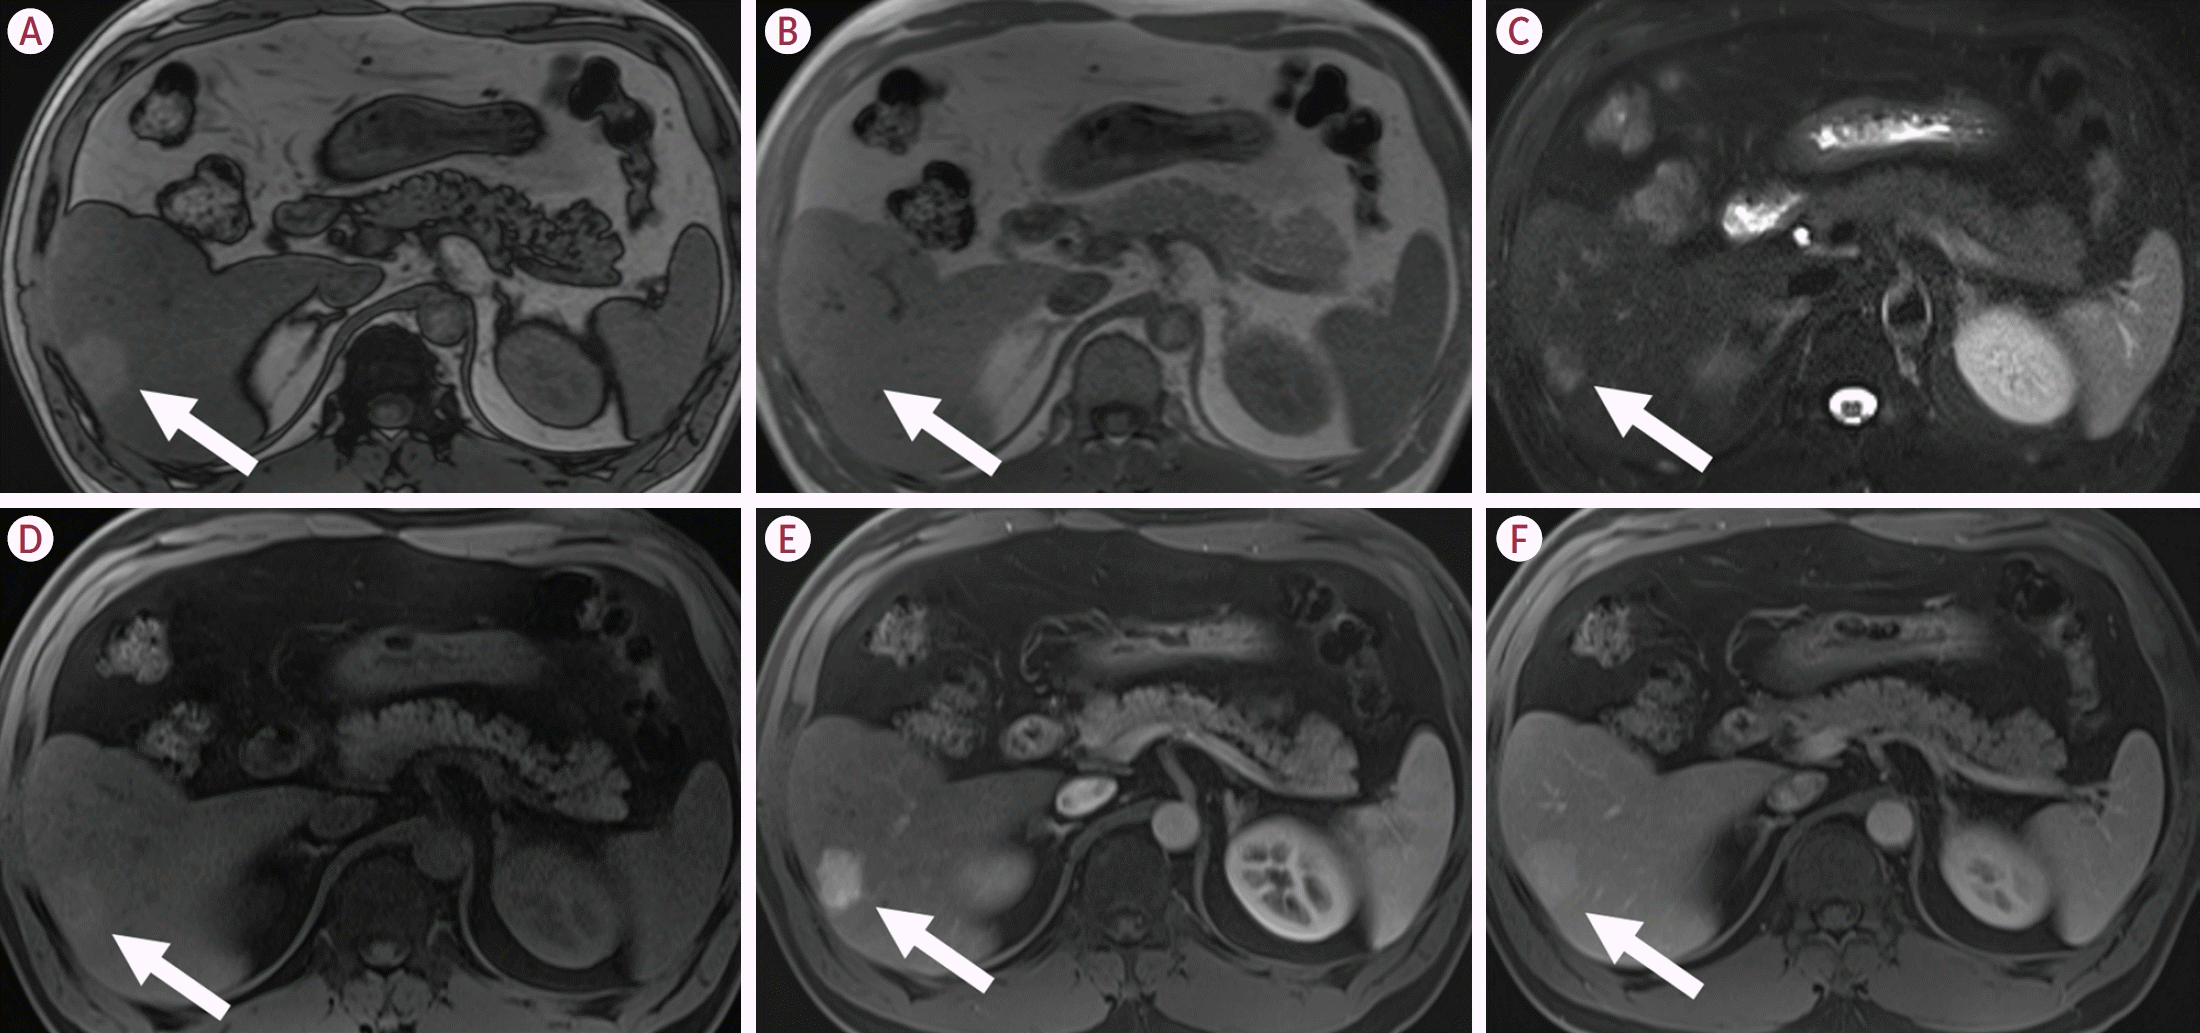

23. Kim TH, Woo S, Ebrahimzadeh S, McInnes MDF, Gerst SR, Do RK. Hepatic adenoma subtypes on hepatobiliary phase of gadoxetic acid-enhanced MRI: systematic review and meta-analysis. AJR Am J Roentgenol. 2023; 220:28–38.

29. Ronot M, Bahrami S, Calderaro J, Valla DC, Bedossa P, Belghiti J, et al. Hepatocellular adenomas: accuracy of magnetic resonance imaging and liver biopsy in subtype classification. Hepatology. 2011; 53:1182–1191.

30. Laumonier H, Bioulac-Sage P, Laurent C, Zucman-Rossi J, Balabaud C, Trillaud H. Hepatocellular adenomas: magnetic resonance imaging features as a function of molecular pathological classification. Hepatology. 2008; 48:808–818.

31. van Aalten SM, Thomeer MG, Terkivatan T, Dwarkasing RS, Verheij J, de Man RA, et al. Hepatocellular adenomas: correlation of MR imaging findings with pathologic subtype classification. Radiology. 2011; 261:172–181.

32. Ba-Ssalamah A, Antunes C, Feier D, Bastati N, Hodge JC, Stift J, et al. Morphologic and molecular features of hepatocellular adenoma with gadoxetic acid-enhanced MR imaging. Radiology. 2015; 277:104–113.

33. Bise S, Frulio N, Hocquelet A, Alberti N, Blanc JF, Laurent C, et al. New MRI features improve subtype classification of hepatocellular adenoma. Eur Radiol. 2019; 29:2436–2447.

39. Tse JR, Felker ER, Naini BV, Shen L, Shen J, Lu DSK, et al. Hepatocellular adenomas: molecular basis and multimodality imaging update. Radiographics. 2023; 43:e220134.

40. Glockner JF, Lee CU, Mounajjed T. Inflammatory hepatic adenomas: characterization with hepatobiliary MRI contrast agents. Magn Reson Imaging. 2018; 47:103–110.